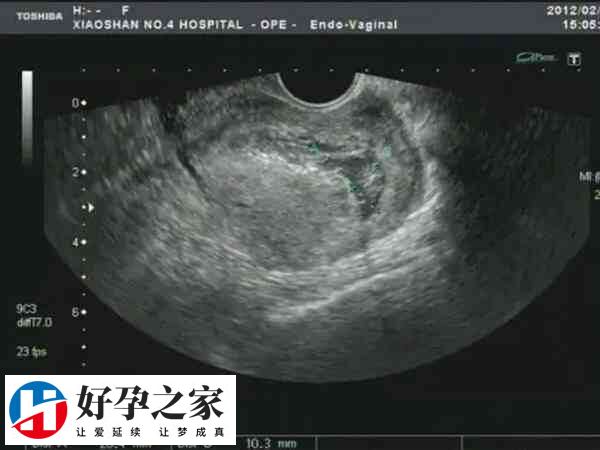

促排双胞胎两个都是空囊是怎么回事

患者做促排双胞胎之后,两个胚胎都是空囊的情况并不多见,而患者之所以出现这类情况,可能是精子或卵子的染...